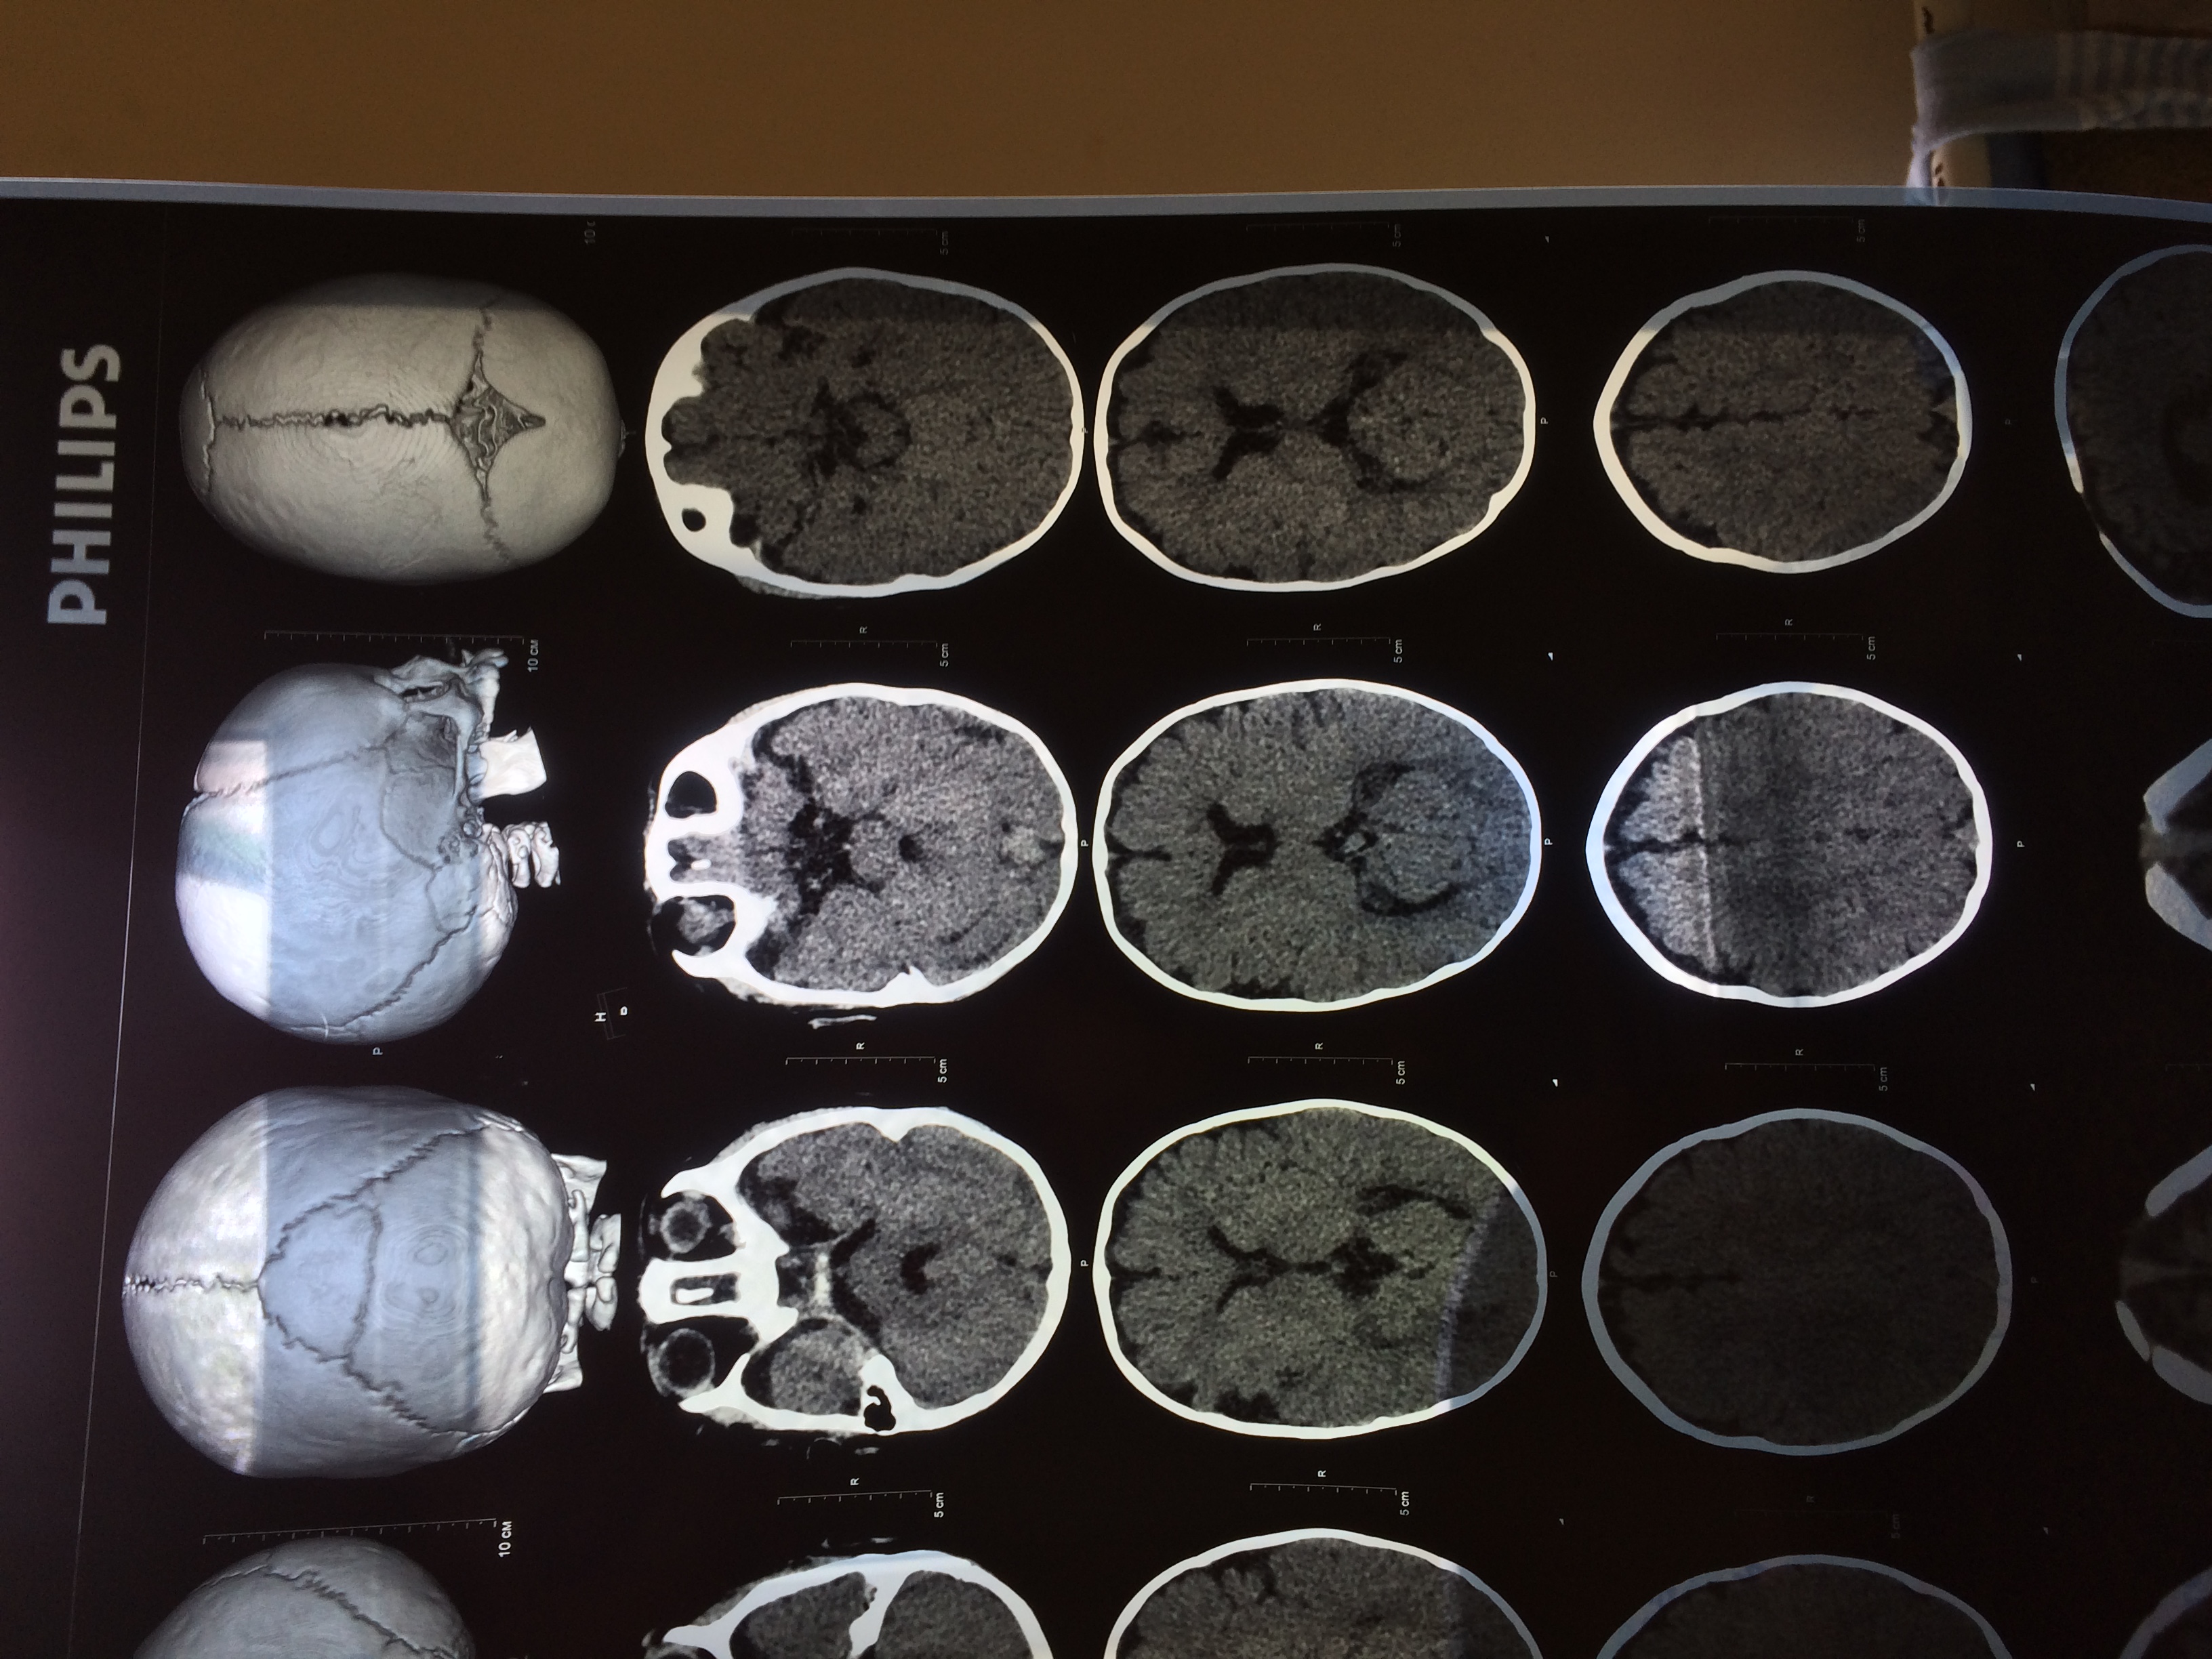

Добрый день! Сыну 7 мес . Родился на 37 неделе путём кесарева сечения. Я на последних неделях беременности 3 раза перенесла орви. Ребёнок родился с тяжёлой двусторонней пневмонией со всеми вытекающими. Был в медикаментозной коме. 12 дней на ивл. За этот период 2 раза были судороги. Реаниматологи сказали что метаболические. До месяца были на отделении опн. Выписаны домой в удовлетворительном состоянии. Наблюдались неврологом по месту жительства. ППЦНС. Пили Пантогам и 2 курса массажа. В 6 месяцев на фоне орви и субфебрильной температуры появились судороги. Фокальные. До 6-8 серий в сутки. Серия по 8-29 приступов. Длятся серии от 1 до 11 минут. Три невролога нас смотрели и без ээг и других методов обследования назначали депакин. Мы все таки добились кт и ээг. На кт-энцефалодисплазия. Похоже, что ещё при рождении все это было. Сейчас принимаем кеппру и депакин. Тут нам собираются только снять приступы, а дальше- сами.

Хочу у Вас проконсультироваться. Мы можем приехать к Вам? Что для этого надо? Какие прогнозы при таком диагнозе. Симптоматическая эпилепсия на фоне энцефалодисплазии.

IMG_5738.JPG

IMG_5737.JPG

IMG_5736.JPG